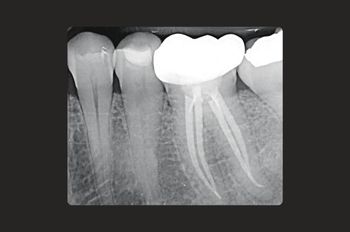

Root canal treatment allows your dentist to remove the infection before it can cause irrevocable damage. It’s a tooth-saving procedure that very often saves a tooth from needing to be extracted.

Your tooth is disinfected and sealed, preventing further bacteria from compromising its structure and health.

An infected root canal can cause intense pain, abscess formation, tooth loss, and even the infection spreading to other parts of the body if left untreated.